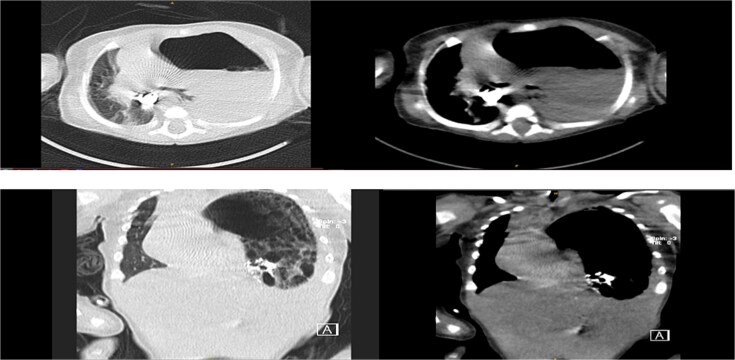

先天性膈疝(CDH)是一种罕见但可能危及生命的异常,由胎儿发育期间膈肌不完全闭合引起,通常在新生儿出现,但很少在婴儿期后期表现为紧张性胃胸,这是胸内胃疝和胃胀的一种严重的症状,可引起严重的呼吸窘迫和纵隔移位;我们描述了一个2个月大的男婴,由于左侧Bochdalek疝,胃扩张占据胸腔,出现突发性呼吸困难和纵隔移位,需要紧急剖腹手术,胃减压和使用不可吸收缝线修复缺陷,导致全肺重新扩张和恢复;本病例强调了晚期CDH合并紧张性胃胸的诊断和治疗挑战,将其与其他呼吸窘迫原因区分开来的重要性,并强调及时识别,及时减压和手术修复对于获得良好结果至关重要,敦促临床医生在影像学显示窘迫婴儿充满空气的半胸时保持高度怀疑。

Congenital diaphragmatic hernia (CDH), a rare but potentially life-threatening anomaly resulting from incomplete diaphragm closure during fetal development, typically presents neonatally but can rarely manifest later in infancy as tension gastrothorax-a critical condition of intrathoracic gastric herniation and distension causing severe respiratory distress and mediastinal shift; we describe a 2-month-old male infant who developed sudden dyspnea and mediastinal shift due to a left-sided Bochdalek hernia with a distended stomach occupying the thoracic cavity, requiring emergent laparotomy with gastric decompression and defect repair using non-absorbable sutures, leading to full lung re-expansion and recovery; this case highlights the diagnostic and therapeutic challenges of late-presenting CDH complicated by tension gastrothorax, the importance of distinguishing it from other causes of respiratory distress, and emphasizes that prompt recognition, timely decompression, and surgical repair are vital for favorable outcomes, urging clinicians to maintain high suspicion when imaging reveals an air-filled hemithorax in distressed infants.